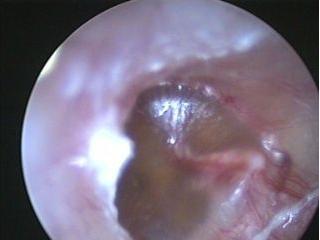

西安新城中大耳鼻喉医院医生表示:用耳内窥镜检查病人的耳部,会发现鼓膜内陷,鼓膜呈淡黄或橙红色,有时透过鼓膜可见气泡。

上面这张显示的是一例慢性分泌性中耳炎的鼓膜图片,鼓膜不透明,如毛玻璃状,鼓膜紧张部有扩张的微血管,多提示鼓室内的为非常粘稠的积液。想知道自身的中耳炎是哪种类型可询问在线咨询